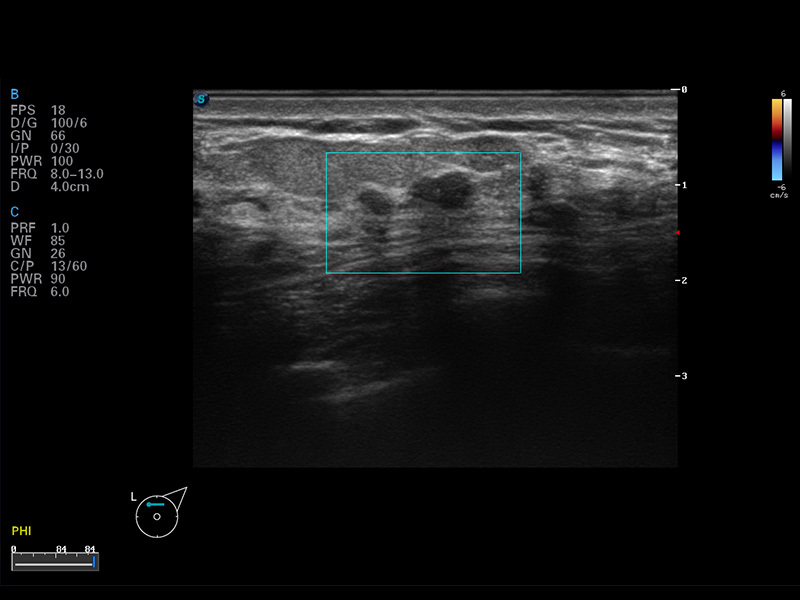

S8 EXP便攜式彩色多普勒超聲診斷儀是開立醫(yī)療研發(fā)的高端全身應(yīng)用型便攜彩超。高通道的VIS平臺融合可視化(Visual)、智能化(Intelligent)和人性化(Smart)的特點,配以開立醫(yī)療自主研發(fā)生產(chǎn)的探頭大家族,使您能夠快速、準確的獲得病人信息,提高工作效率的同時減輕疲勞。

成像技術(shù)

μ-Scan微米成像

諧波成像

空間復(fù)合成像